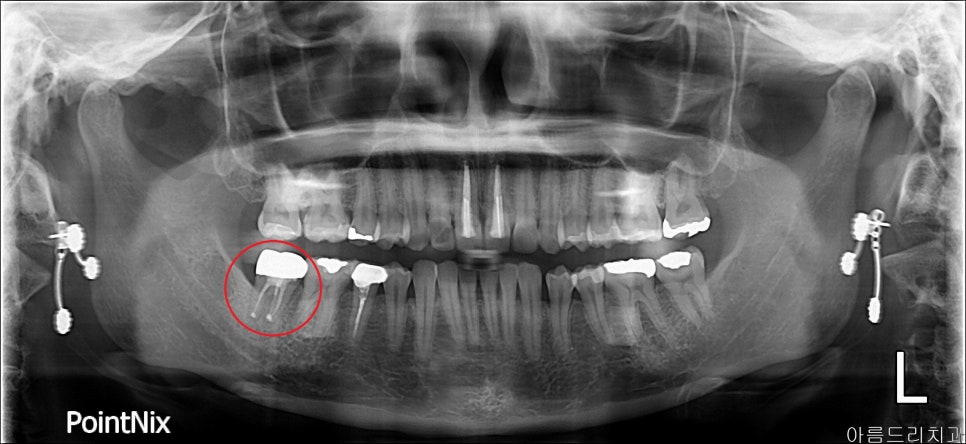

치아를 뽑았다가 그 자리에 다시 심는 치아 재식술

치아 재식술이 뭔가요? 치아를 뽑아서, 눈으로 염증 부위를 직접 확인 후 처치하여 뽑은 부위에 다시 재식립하는 시술을 말합니다.

재식 _ 전

얼마 전 조00이라는 환자분이 신경치료를 모두 마친 후 금으로 크라운까지 세팅된 치아에 통증을 호소하시면서 내원하셨습니다. 아직 나이도 어리고, x-ray나 CT로 염증을 확인하기 어려웠습니다.

이러한 경우 발치하고 임플란트를 해야 하나요?라고 질문하시더군요. 발치하기 전 치아를 살릴 수 있는 재식술에 대해 설명 들으시고 당일 바로 진행되었습니다.

재식_전 파노라마 재식_후 파노라마